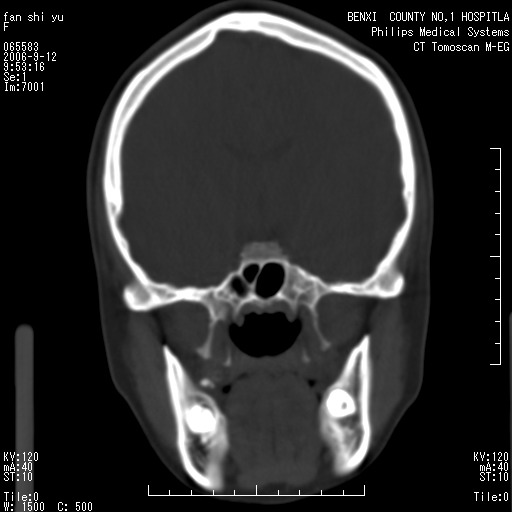

标题: CT4607:看看这个头颅冠状位。

女,22岁,自觉头顶部质硬包块.

巨大蛛网膜粒压迹。

巨大蛛网膜粒压迹